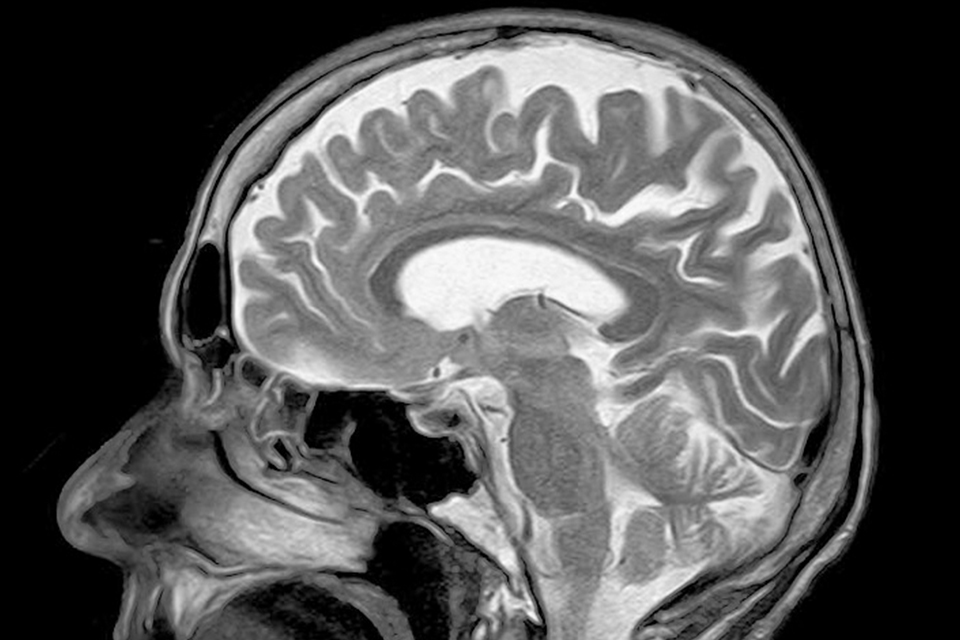

根據Axios的報導,Wisconsin大學和Pennsylvania大學分析了英國生物銀行中共36000多名男性和女性的腦部的核磁共振影像,研究團隊在排除吸菸、年齡、性別、BMI、吸菸和社會經濟地位等變量影響後,得出了這樣的結論。

從MRI顯示的影像來看,每天攝取的酒量若從1、2單位增加到3個單位,就能看出大腦部位的灰質和白質逐漸減少。而且喝的酒量越多,大腦衰老的幅度就越大,每天喝4杯酒,長期下來,大腦相當於老化10多年。